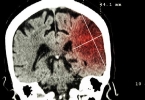

3.手术治疗:

在一些由肿瘤或严重血管病变引起的眩晕患者中,可能需要进行手术治疗以解决根本问题。